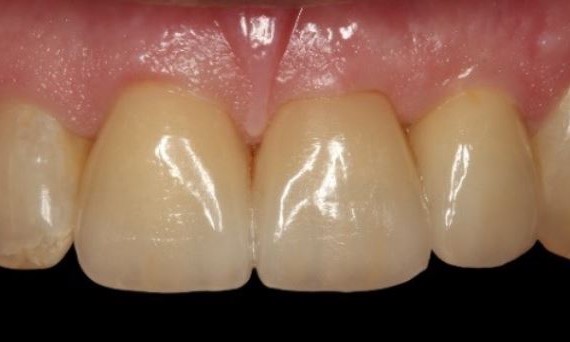

Exzellente Ästhetik

Langfristiger marginaler Knochenerhalt für eine exzellente Ästhetik über Jahre hinweg. Sie wissen, dass Sie gewonnen haben, wenn Ihr anspruchsvollster Patient dauerhaft zufrieden ist.

Langfristiger Knochenerhalt und exzellente Ästhetik dokumentiert und klinisch erprobt.

Die Hauptmerkmale des Implantats – EV-Innenverbindung, OsseoSpeed, MicroThread, Soft Tissue Chamber – wurden für das Astra Tech Implant System hinsichtlich Knochenerhalt und Ästhetik dokumentiert und klinisch erprobt.

SoftTissue Chamber – größeres Weichgewebevolumen und hohe Ästhetik